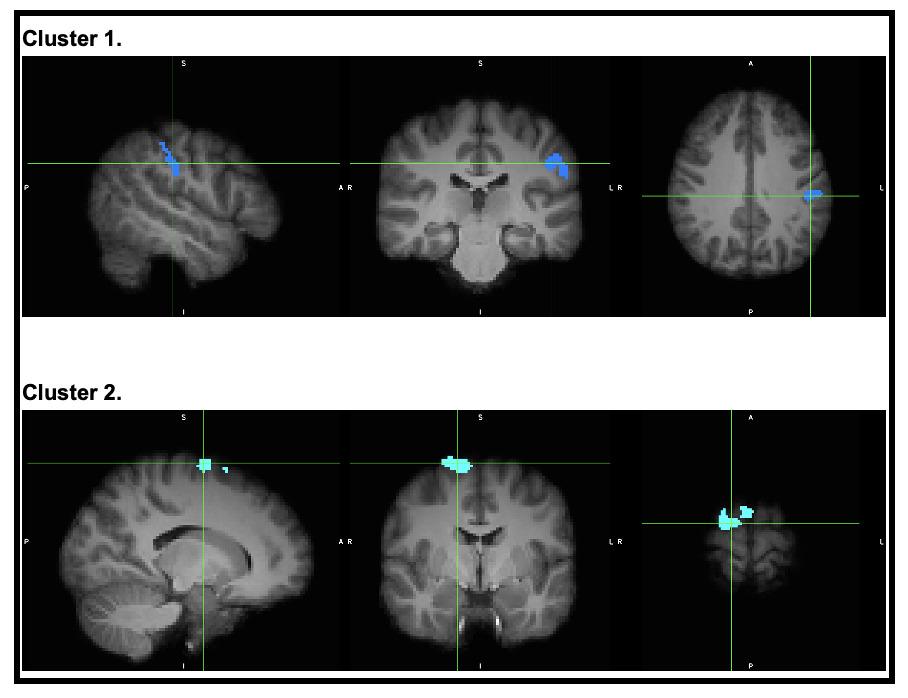

Significantly higher beta-2 power over the frontal region of interest was observed at the first measurement time point in the non-involved limb of the ACL group in comparison to the control group (p = 0.03). Despite individual variation, no other statistically significant differences were identified for JPS error, neuromuscular, or other cortical activity

Variation in cortical activity between the ACL and control group were present, which is consistent with published results in later stages of rehabilitation. Both indicate the importance of a neuromuscular and neurocognitive focus in the rehabilitation.

Descriptive statistics of the normalized cortical activity over the entire JPS test per frontal, central and parietal region of interest, as well as frequency bands, are displayed in Table 5 Residual analysis demonstrated no evidence against model assumptions. No significant differences were observed in the fixed effects estimates for frontal theta (0.16 < p < 0.99; AIC = 3613.4; R2 = 0.34) and frontal beta-1 (0.06 < p < 0.47; AIC = 3550.5; R2 = 0.35) (Table 5). A signif-

icantly different fixed effect estimate was found for frontal beta-2 when comparing the ACL-M1-non-involved leg to the control group (p = 0.03). The remaining comparison of frontal beta-2 did not yield a statistically significant difference (0.32 < p < 0.75, AIC = 3468.2; R2 = 0.27) (Table 5).

healthy control group, with the exception of the beta-2 frequency band in the frontal region of interest for the noninvolved leg of the ACL group, which demonstrated a difference at the first measurement time point in comparison to the control group.

A higher mean frontal theta power was observed in both limbs of the ACL group in the first two measurement time points, although this did not reach statistical significance when compared to a healthy control group. Baumeister et al.18 reported significantly higher theta power over the frontal cortical areas in both limbs of participants on average one year after ACL reconstruction compared to healthy controls.18 Elevated frontal theta power might represent a higher need for attention during the JPS test execution.44, 45

Beta oscillations are thought to be involved in top-down processing and sensorimotor integration and are linking different brain regions, including the pre-motor and somatosensory cortex, the supplementary motor areas and the cerebellum.44,52 The literature indicates that fluctuations in beta oscillations can be divided into movementbased reductions, with a decrease in beta power slightly prior to and during movement, and post-movement beta rebound, which is characterized by an elevation of beta power following movement.52 It should be noted that the referenced study did not distinguish between beta-1 and beta-2. Apart from frontal beta-2 in one comparison, no other significant results were found in the present study 51 A detailed analysis regarding the movement phase would provide valuable insights into the differences in movement planning, execution and the integration of sensory information. Moreover, examining cortical activity in repetitions with higher angular error could prove beneficial. One fMRI study reported a significantly positive correlation between angular error and brain activity 17 Further investigation could clarify how proprioceptive error detection and integration contribute to the execution of precise movements and the association with cortical activities. This could be used to evaluate the high re-injury rates among patients with ACL reconstruction.